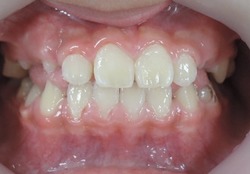

初診時乳臼歯にレジンを盛る事で咬み合わせの高さを治療していきます。

乳臼歯にレジンを盛る事で第一大臼歯の咬み合わせに隙間が出来ました。

約2か月で隙間が埋まり第一大臼歯が咬み合いました。

上顎から矯正装置を装着していきます。

8歳の女子 受け口(下顎前突)

術前

7歳の女子 受け口(下顎前突)

9歳7か月 男子 治療前

乳臼歯にレジンを盛る事で、咬み合わせの高さを改善していきます。